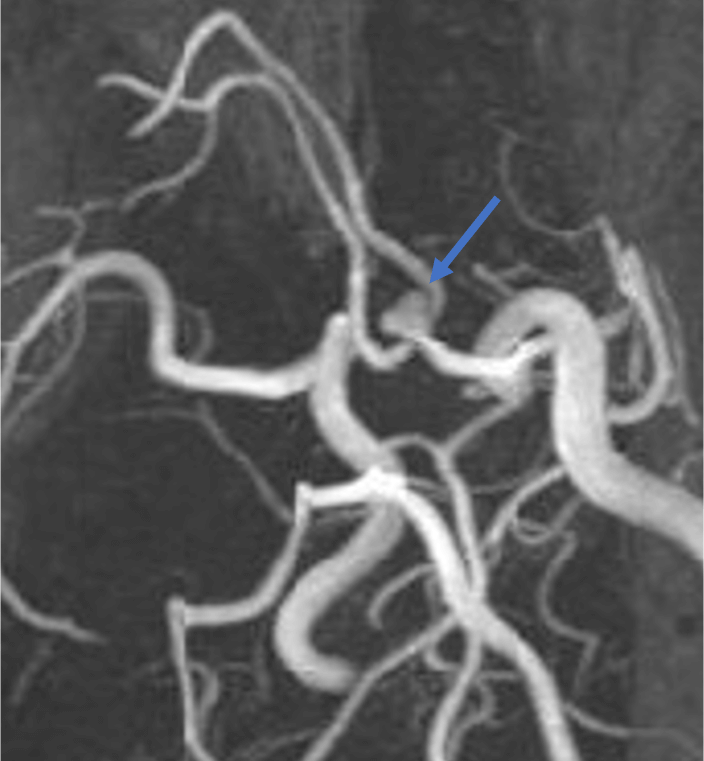

頭部CTAでのブレブを伴った前交通動脈瘤の1例

症例は60代女性。めまいを主訴に近医脳神経外科を受診した。高血圧を認めたほか頭部MRIで前交通動脈瘤を指摘され、精査・加療目的で当院脳神経外科を紹介受診した。頭部CTAでは前交通動脈にブレブを伴う6mm大の嚢状動脈瘤を認めた。検討会、本人との相談にて、クリッピング術の方針となった。検査2ヶ月後に開頭クリッピング術が施行され、合併症なく退院した。その後、再発なく経過している。

動脈瘤の形状に関しては、不整な膨らみ(ブレブ)がある場合、破裂リスクが約1.6倍高まることが知られています。ただし、ブレブは小さな突出として認められることもあるため、詳細な評価には高い空間分解能を有するCTAが有用です。

提示症例は、ブレブを有する前交通動脈瘤のケースですが、CTA・MRAの両方で動脈瘤の不整な形態は視認可能です。ただし、CTAの方がより詳細にブレブを描出できていることがわかります。